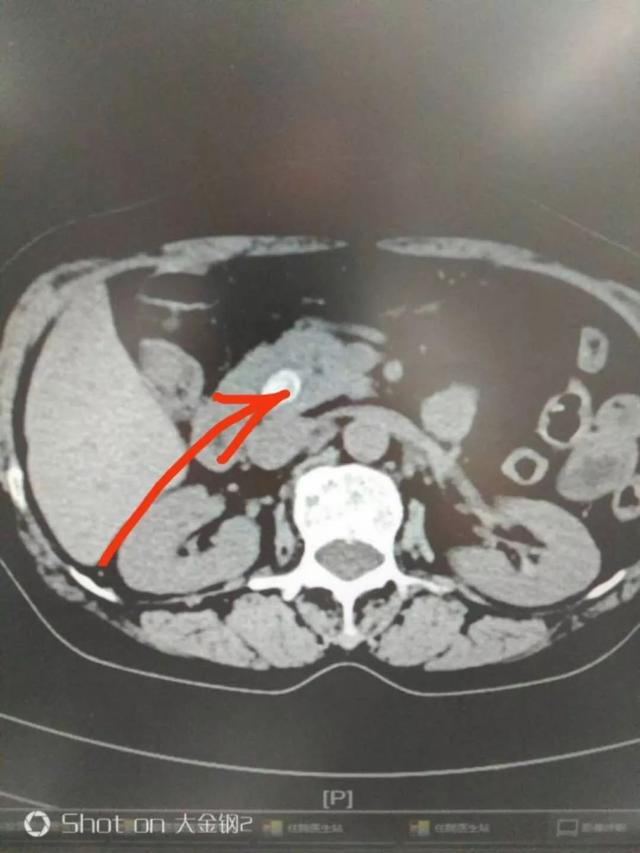

今天上门诊,一大早来了位病人,带着一张片子来。一看这不是胆总管结石吗?这石头还不小,肝内外胆管也扩张了。